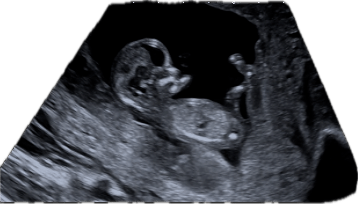

With each embryo transfer, we have come up with a silly name we called the embryo. Friends often help us come up with these names. The first one was Cletus the Fetus. Then I think there may have been Ketchup and Bacon. There is no real rhyme or reason to what the name will be, but this embryo was called Peppa (short for pepperoni and courtesy of my best friends). Below is little Peppa at 12 weeks. And no, we will not actually name the child Peppa (although it is kind of cute).

I can safely say we have made it through the first trimester and our 12-week ultrasound looked great. I started to show fairly early and can’t imagine what I will look like in the third trimester!